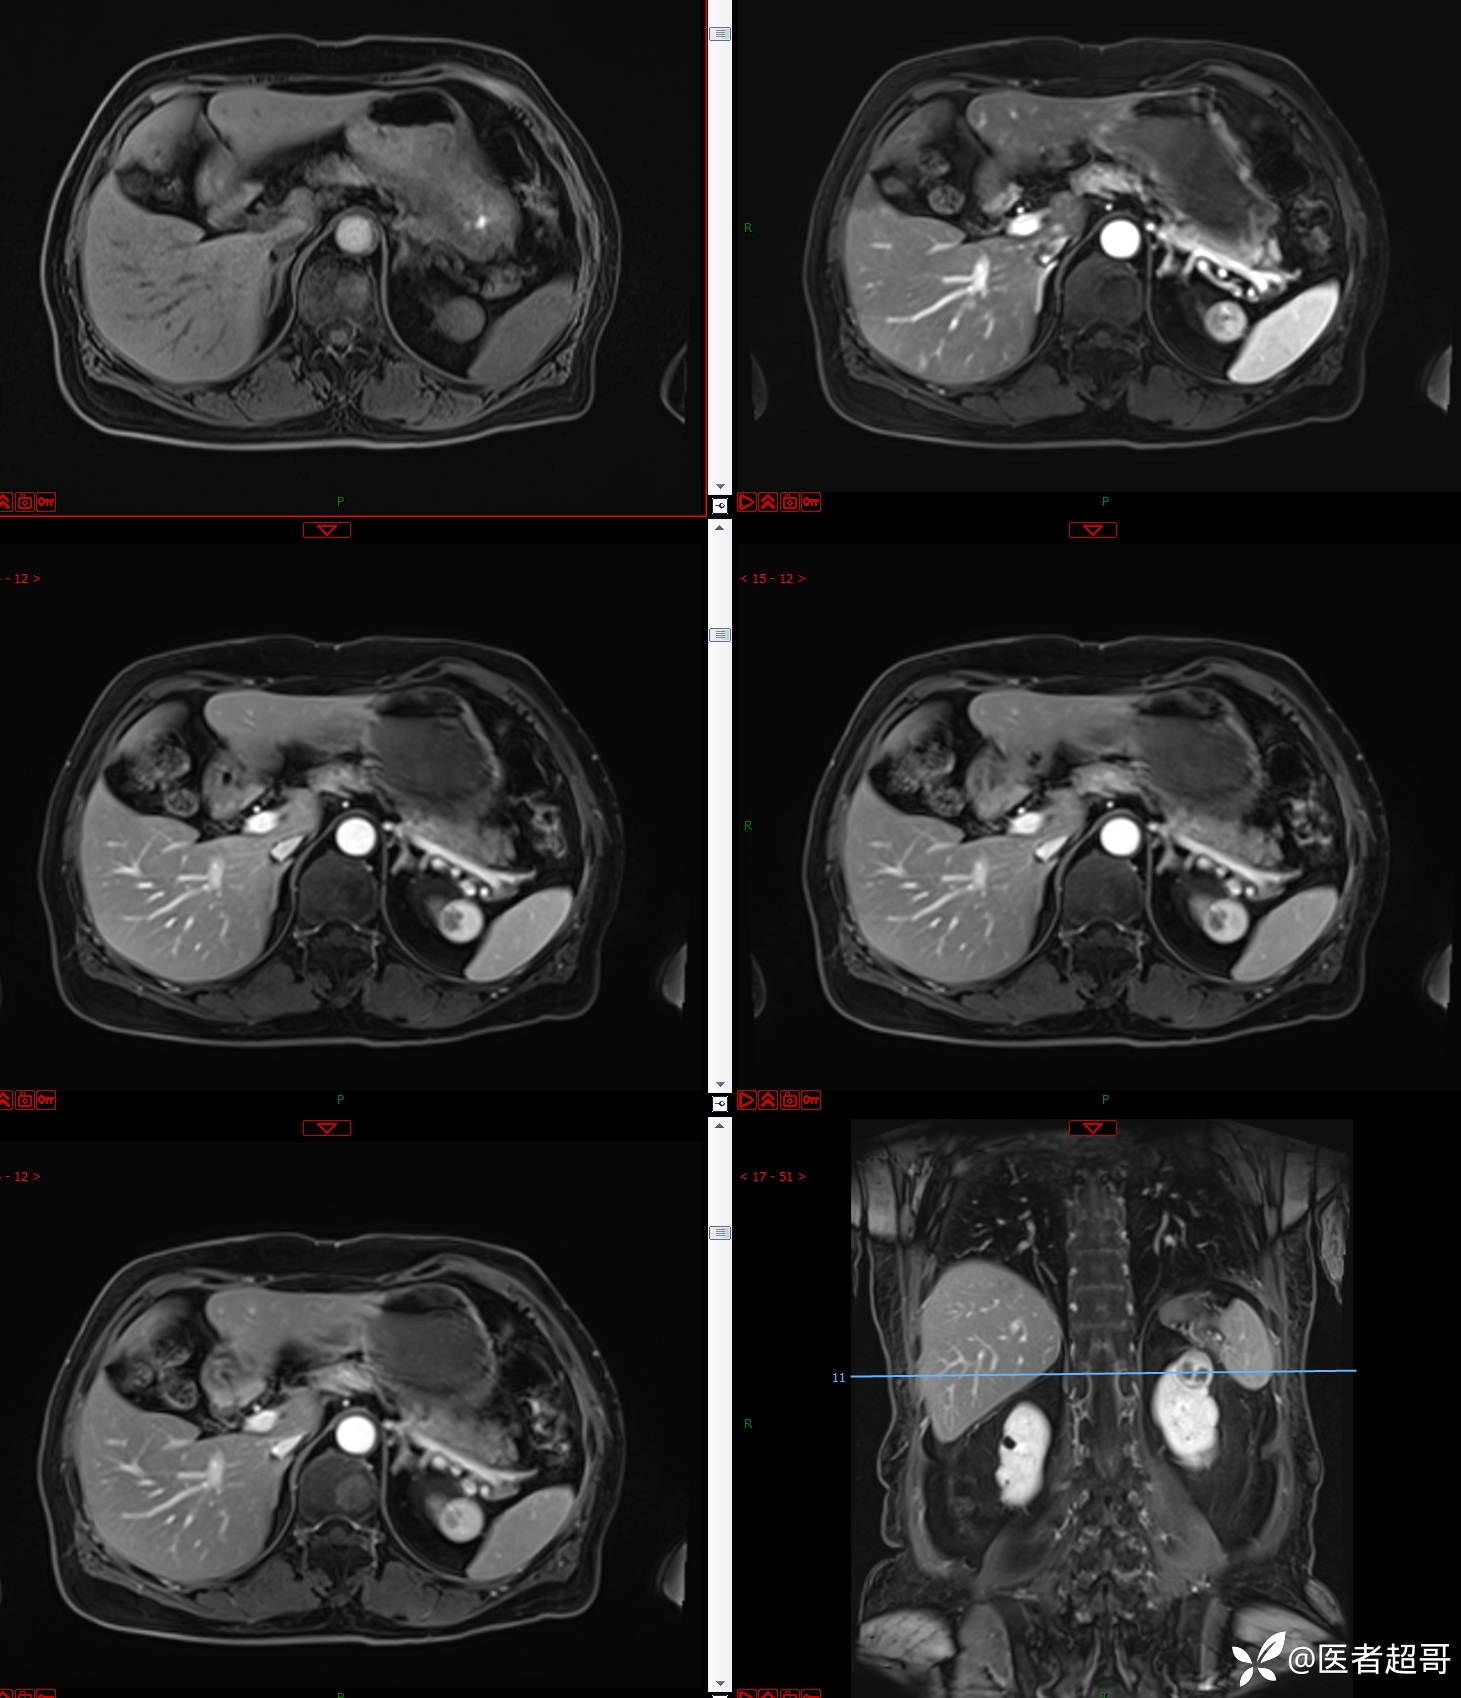

左肾占位2个月就诊,有病理,请分析!

患者 女 73岁

主 诉:查体发现左肾占位2月。

现病史:患者自述2月前于镇中心卫生院行腹部超声发现:左肾实性占位。患者无尿频尿急尿痛,无发热寒战,无恶心呕吐。未行特殊治疗。现患者为求进一步诊治,就诊我院,门诊以“肾肿物”为诊断收入院,患者自发病以来,神志清,精神可,饮食可,睡眠一般,大便正常,体重未见明显改变。